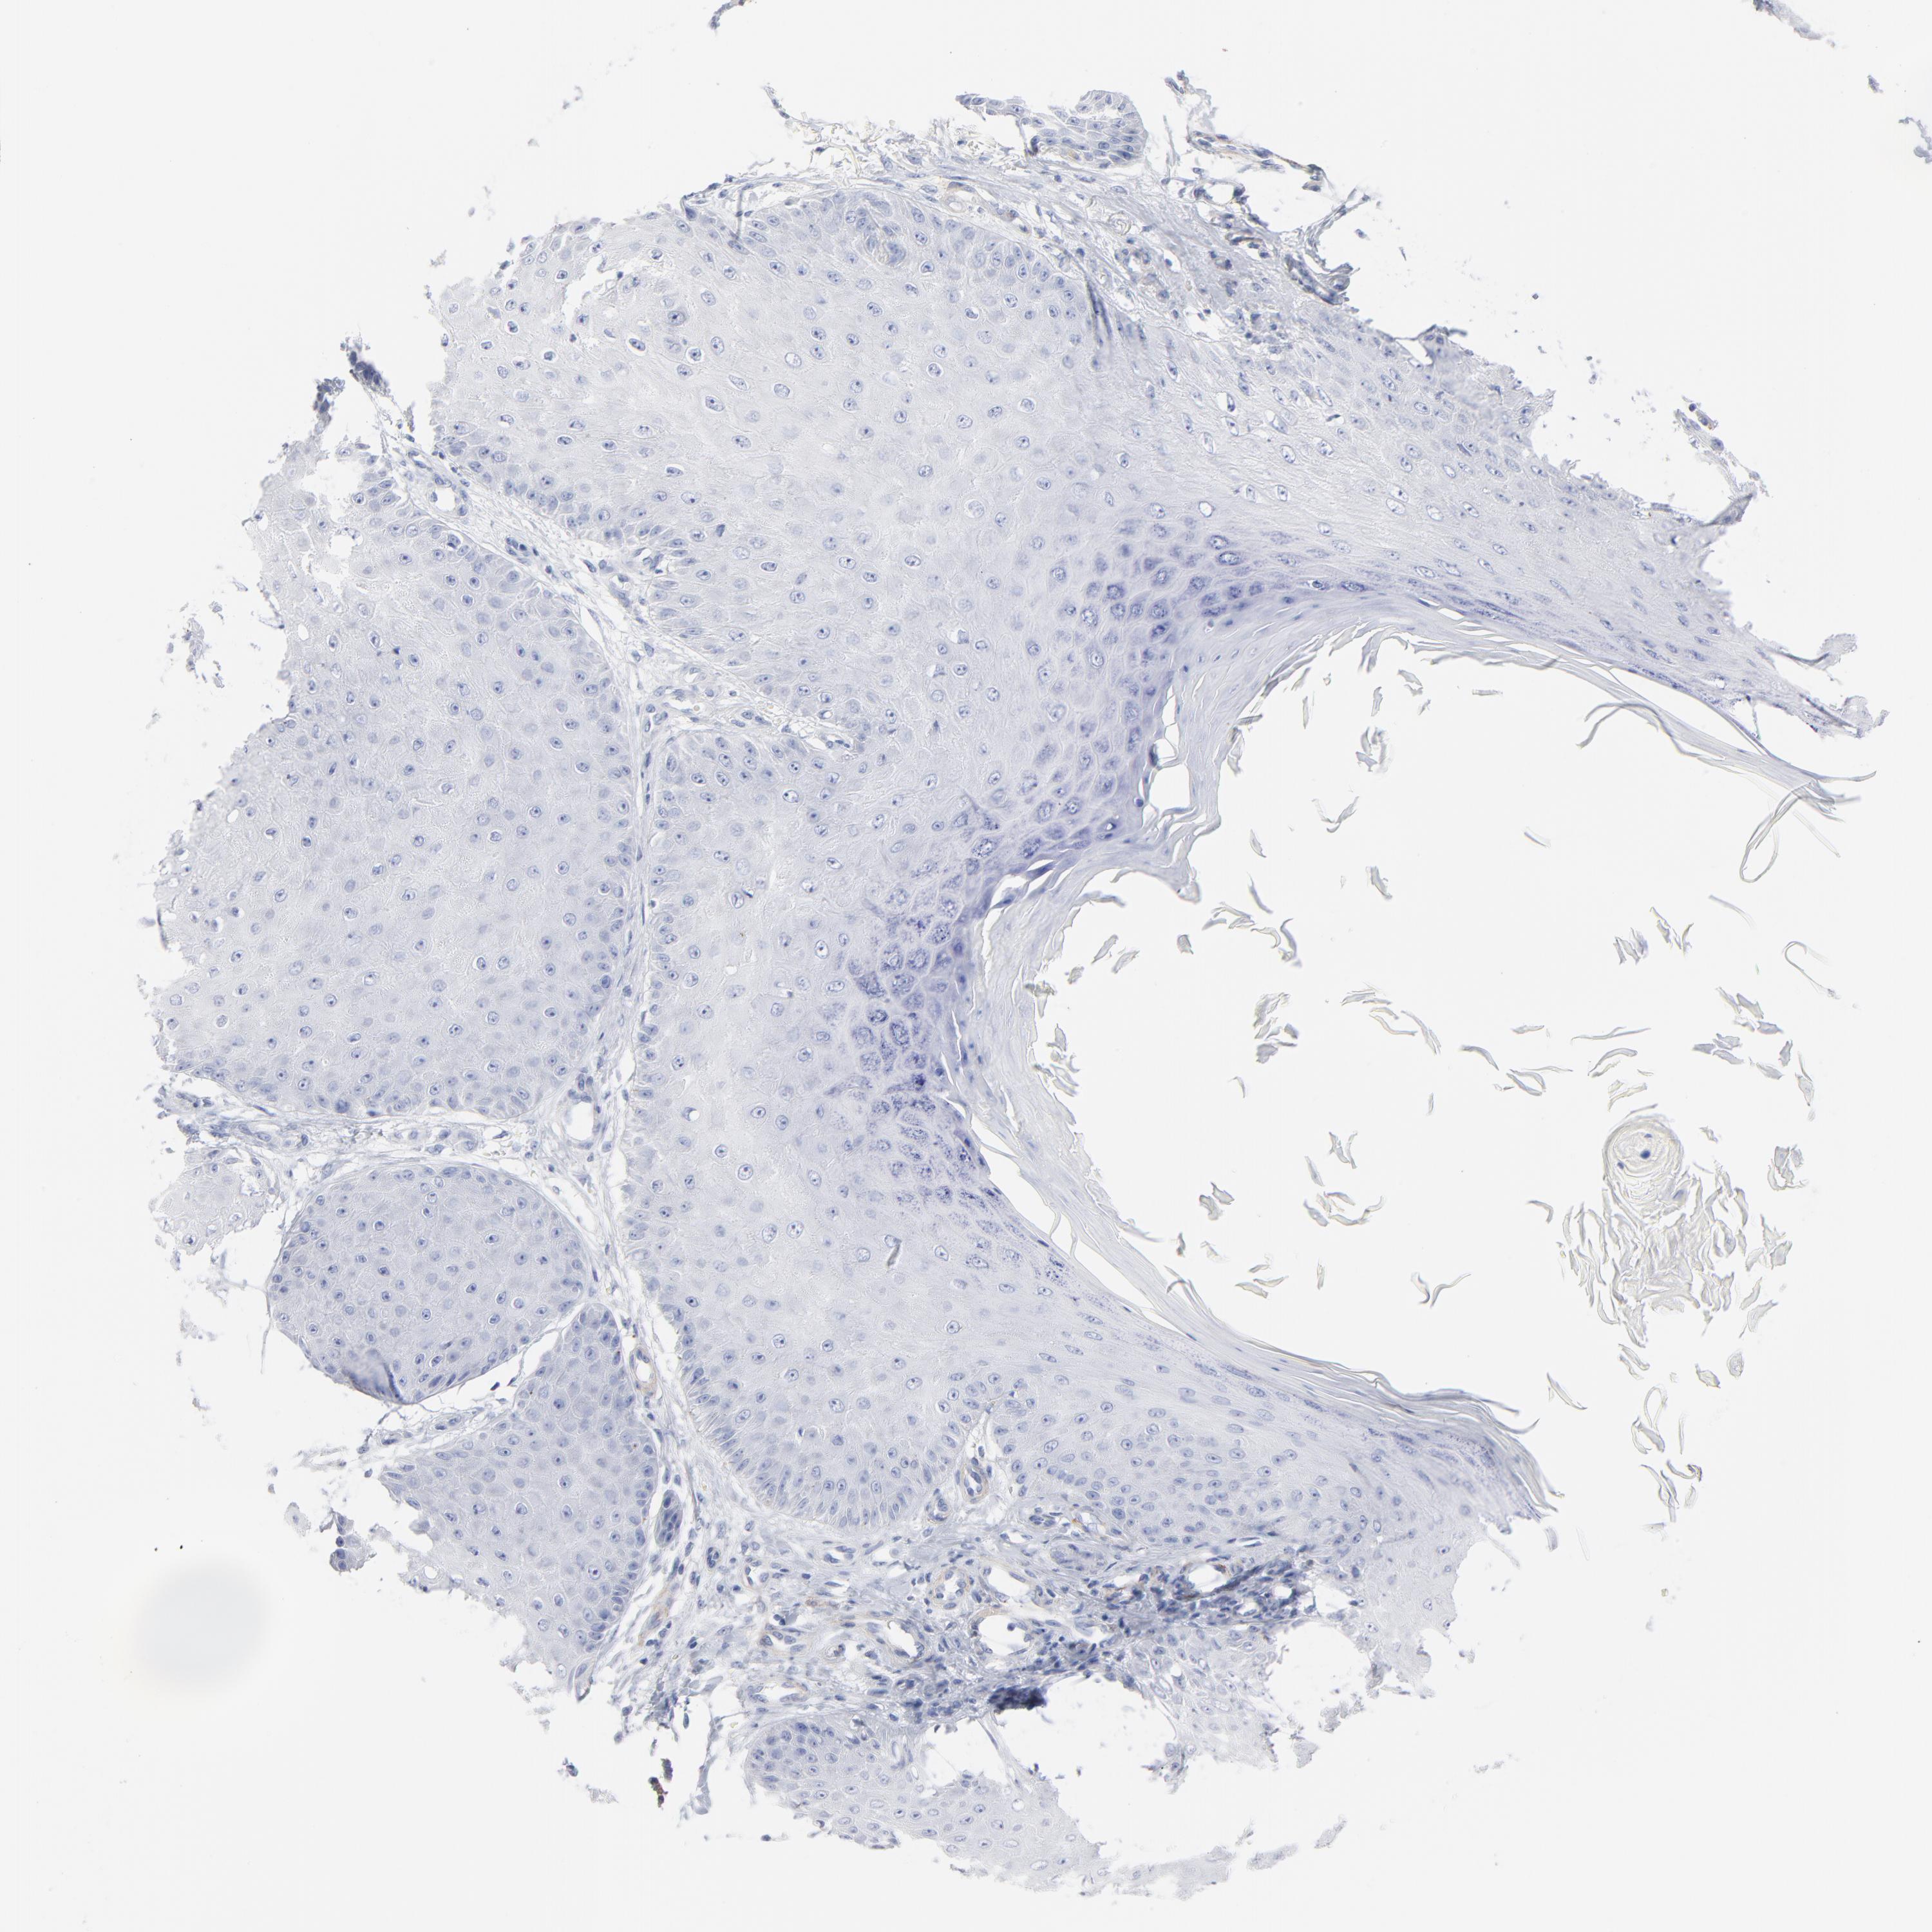

SKIN CANCER - Protein expressioni

A mouse-over function shows sample information and annotation data. Click on an image to view it in a full screen mode. Samples can be filtered based on level of antibody staining by selecting one or several of the following categories: high, medium, low and not detected. The assay and annotation is described here.

Antibody stainingi

Antibody staining in the annotated cell types in the current human tissue is reported as not detected, low, medium, or high, based on conventional immunohistochemistry profiling in selected tissues. This score is based on the combination of the staining intensity and fraction of stained cells.

Each image is clickable and will lead to virtual microscopy that enables deeper exploration of all samples and also displays staining intensity scores, fraction scores and subcellular localization as well as patient and tissue information for each sample.

Antibody HPA003596

Squamous cell carcinoma, NOS

Basal cell carcinoma